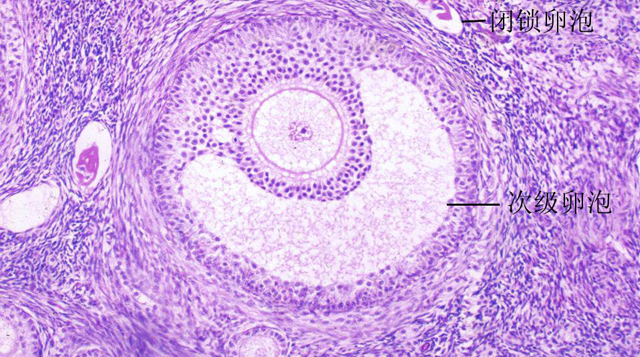

优势卵泡就是指卵泡中个头最大的那个卵泡,根据卵泡发育生长过程,卵泡可分为三个阶段,如:原始卵泡、生长卵泡、成熟卵泡。

原始卵泡是指一个初级卵母细胞以及其周边的卵泡细胞,这个初级卵母细胞在通过发育生长,就会成为成熟卵泡,一般女性在正常月经周期内、正常的排卵都只会出现一个优势卵泡,只有一个卵子会排出。